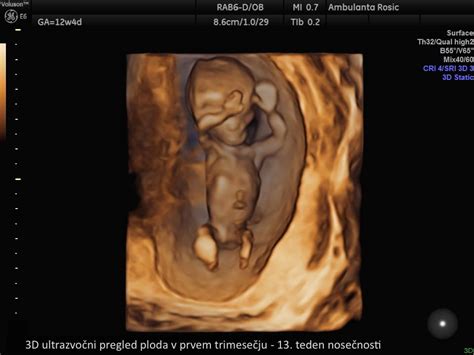

Spremljanje rasti ploda poteka skozi celotno nosečnost z ultrazvočnimi pregledi. Velikost in teža ploda se spreminjata iz tedna v teden, vendar je pomembno poudariti, da so navedene številke zgolj okvirne povprečne vrednosti. Vsak otrok raste s svojo individualno hitrostjo, zato se lahko velikost in teža vašega otroka bistveno razlikujeta od povprečja. Vaš ginekolog bo na podlagi ultrazvočnih meritev in drugih dejavnikov ocenil, ali je z rastjo vašega otroka vse v redu.